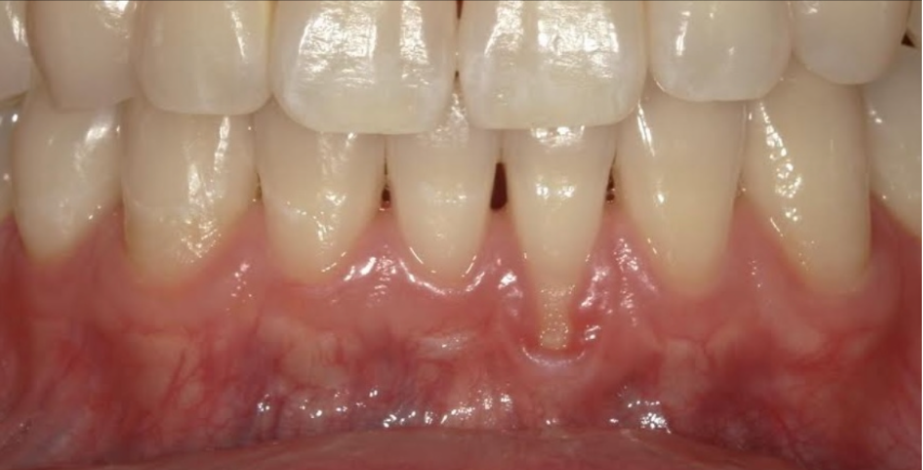

歯肉退縮が気になり来院されました

before

| ① 患者様の主訴 | 歯肉退縮 |

| ③ 治療内容 | 歯肉移植(結合組織移植) |

| ④ 治療後経過 | 良好 |

| ⑤ 治療期間 | 1ヶ月 |

| ⑥ 治療費用 | 約10万円 |

| ⑦ リスク・副作用 | 外科処置に伴う出血、腫脹、疼痛 |